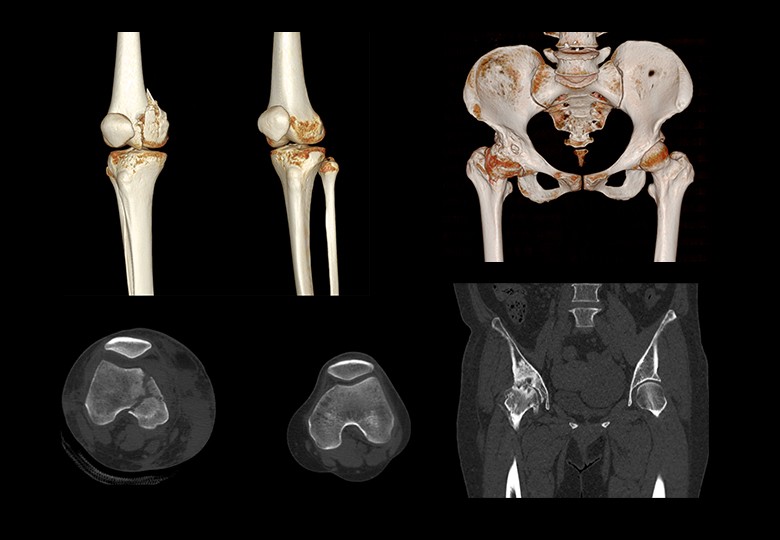

Album d'images cliniques

• Os